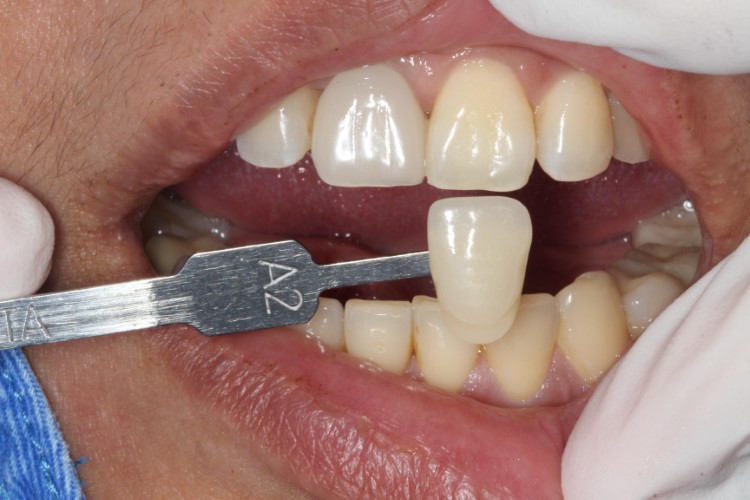

▲從數位照片可以看出,手術當天立即有牙,大幅改善門面的美觀問題

▲植體植入後鎖上臨時固定假牙,立即有牙不擔心美觀問題